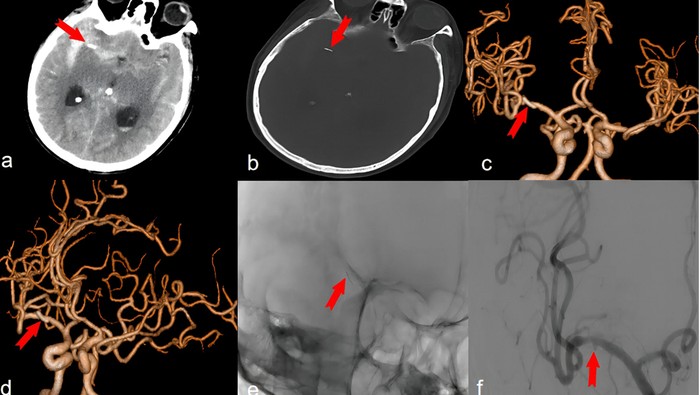

Berdasarkan hasil pemindaian, terlihat ada jarum akupunktur berwarna emas dan agak runcing sepanjang setengah inci atau sekitar 1,27 cm itu bersarang di dalam arteri otak pria tersebut. Hal itu menyebabkan perdarahan internal yang berdampak pada masalah ingatannya.

Dokter mendiagnosis pria tersebut mengidap pseudoaneurisma intrakranial, yaitu kondisi ketika darah bocor keluar dari pembuluh darah di otak namun tertahan oleh jaringan di sekitarnya. Penyakit ini berbeda dengan aneurisma dan sangat jarang terjadi.

Jarum akupunktur tertancap di otak pria selama 20 tahun Foto: Journal of Medical Case Reports |

Lebih lanjut, dokter terlebih dahulu harus memotong sebagian tengkoraknya atau prosedur yang disebut kraniotomi untuk melihat otaknya. Dokter kemudian memotong dura mater atau lapisan luar otak yang tebal, dan menggunakan mikroskop bedah untuk menavigasi otak dan jarum akupunktur yang tertancap tersebut. Ini bertujuan untuk menghindari arteri dan struktur vital.

Jarum kemudian dicabut, dan pembuluh darah yang pecah ditutup menggunakan klip logam yang sangat kecil untuk menutup bagian pembuluh yang pecah.